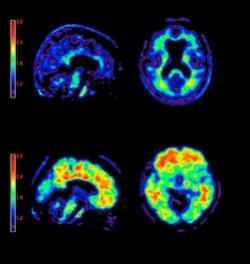

Computed tomography (CT) and magnetic resonance imaging (MRI) have been used for years to rule out other causes of dementia. More recently, positron emission tomography (PET) and cerebral metabolism using fluoro-deoxy-D-glucose (FDG) have been used to show characteristic changes in the brain and help rule in Alzheimer’s pathophysiological processes.

In April the U.S. Food and Drug Administration (FDA) approved Avid Radiopharmaceuticals’ (now part of Eli Lilly) Amyvid, a brain plaque diagnostic tool using florbetapir (F-AV-45). This radiotracer agent is delivered intravenously and is drawn to beta-amyloid plaque, a characteristic of AD. This allows a physician to see accumulations of amyloid in the brain, which in turn help the physician to determine whether a patient is suffering from some form of dementia, but cannot confirm a diagnosis of AD. Other diseases such as Parkinson’s disease, Huntington’s disease and Creutzfeldt-Jakob disease characteristically present with plaques as well, therefore physicians must still use mental and behavior cues to diagnose a patient with AD.

Amyvid is the only FDA-approved diagnostic PET tracer for imaging plaques in vivo, but there looks to be another agent in the pipeline that could potentially provide more diagnostic armament for detecting AD. Navidea Biopharmaceuticals’ AZD4694 Fluorine-18 labeled dye has completed Phase IIa clinical trials, and Phase III clinical trials will likely begin in 2013. This entity has been shown to be highly sensitive in detecting amyloid plaque. The signal-to-noise ratio remains low due to low background and white matter uptake, thus providing clear images of amyloid plaques. Navidea hopes AZD4694 will be used as an early identification tool for AD.